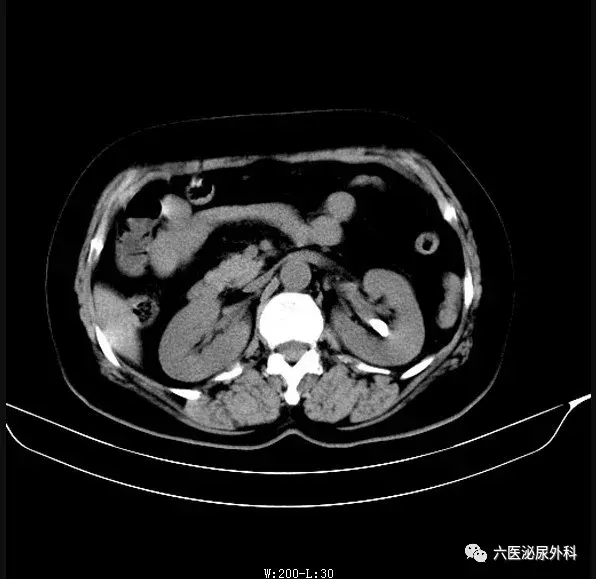

可以看到该患者有三颗结石,一颗位于肾盂输尿管出口处,一颗位于肾中盏,还有一颗位于囊肿内(暂不考虑这颗)